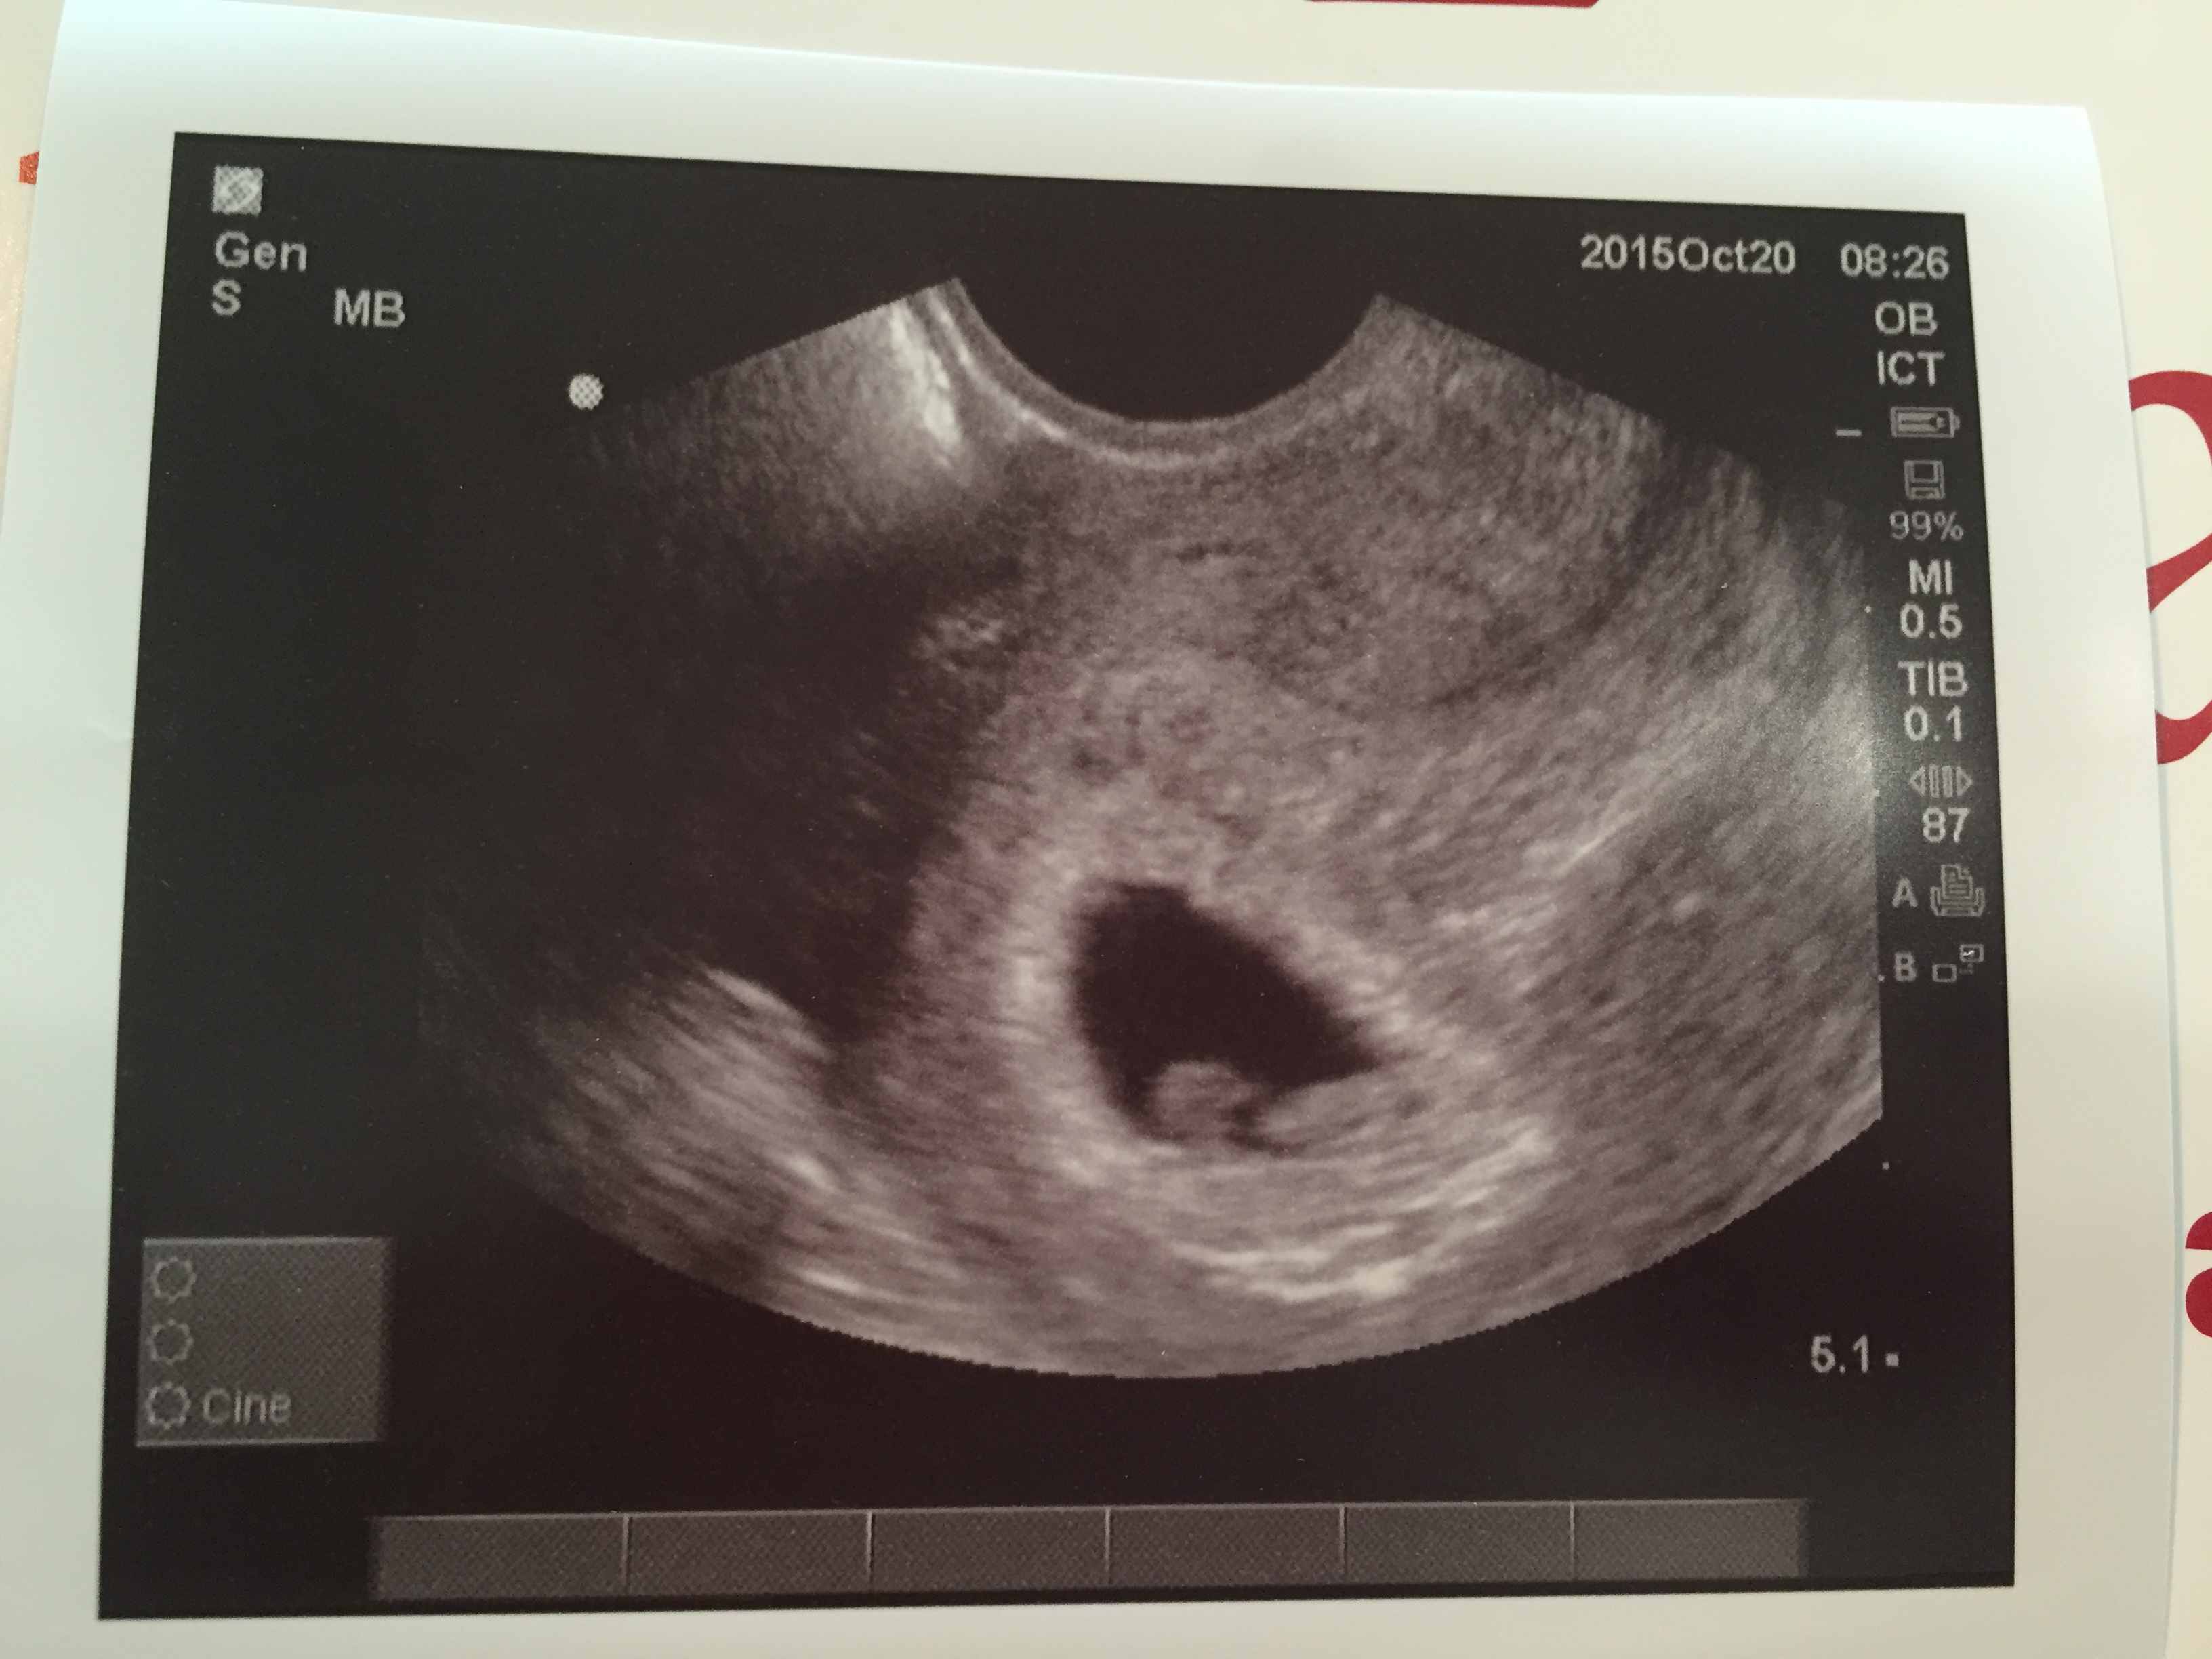

Had my first ultrasound today...5w3d and sure enough there is a sack and yolk sack....super excited!!!! Ill have another done in a couple weeks to look for a heartbeat!